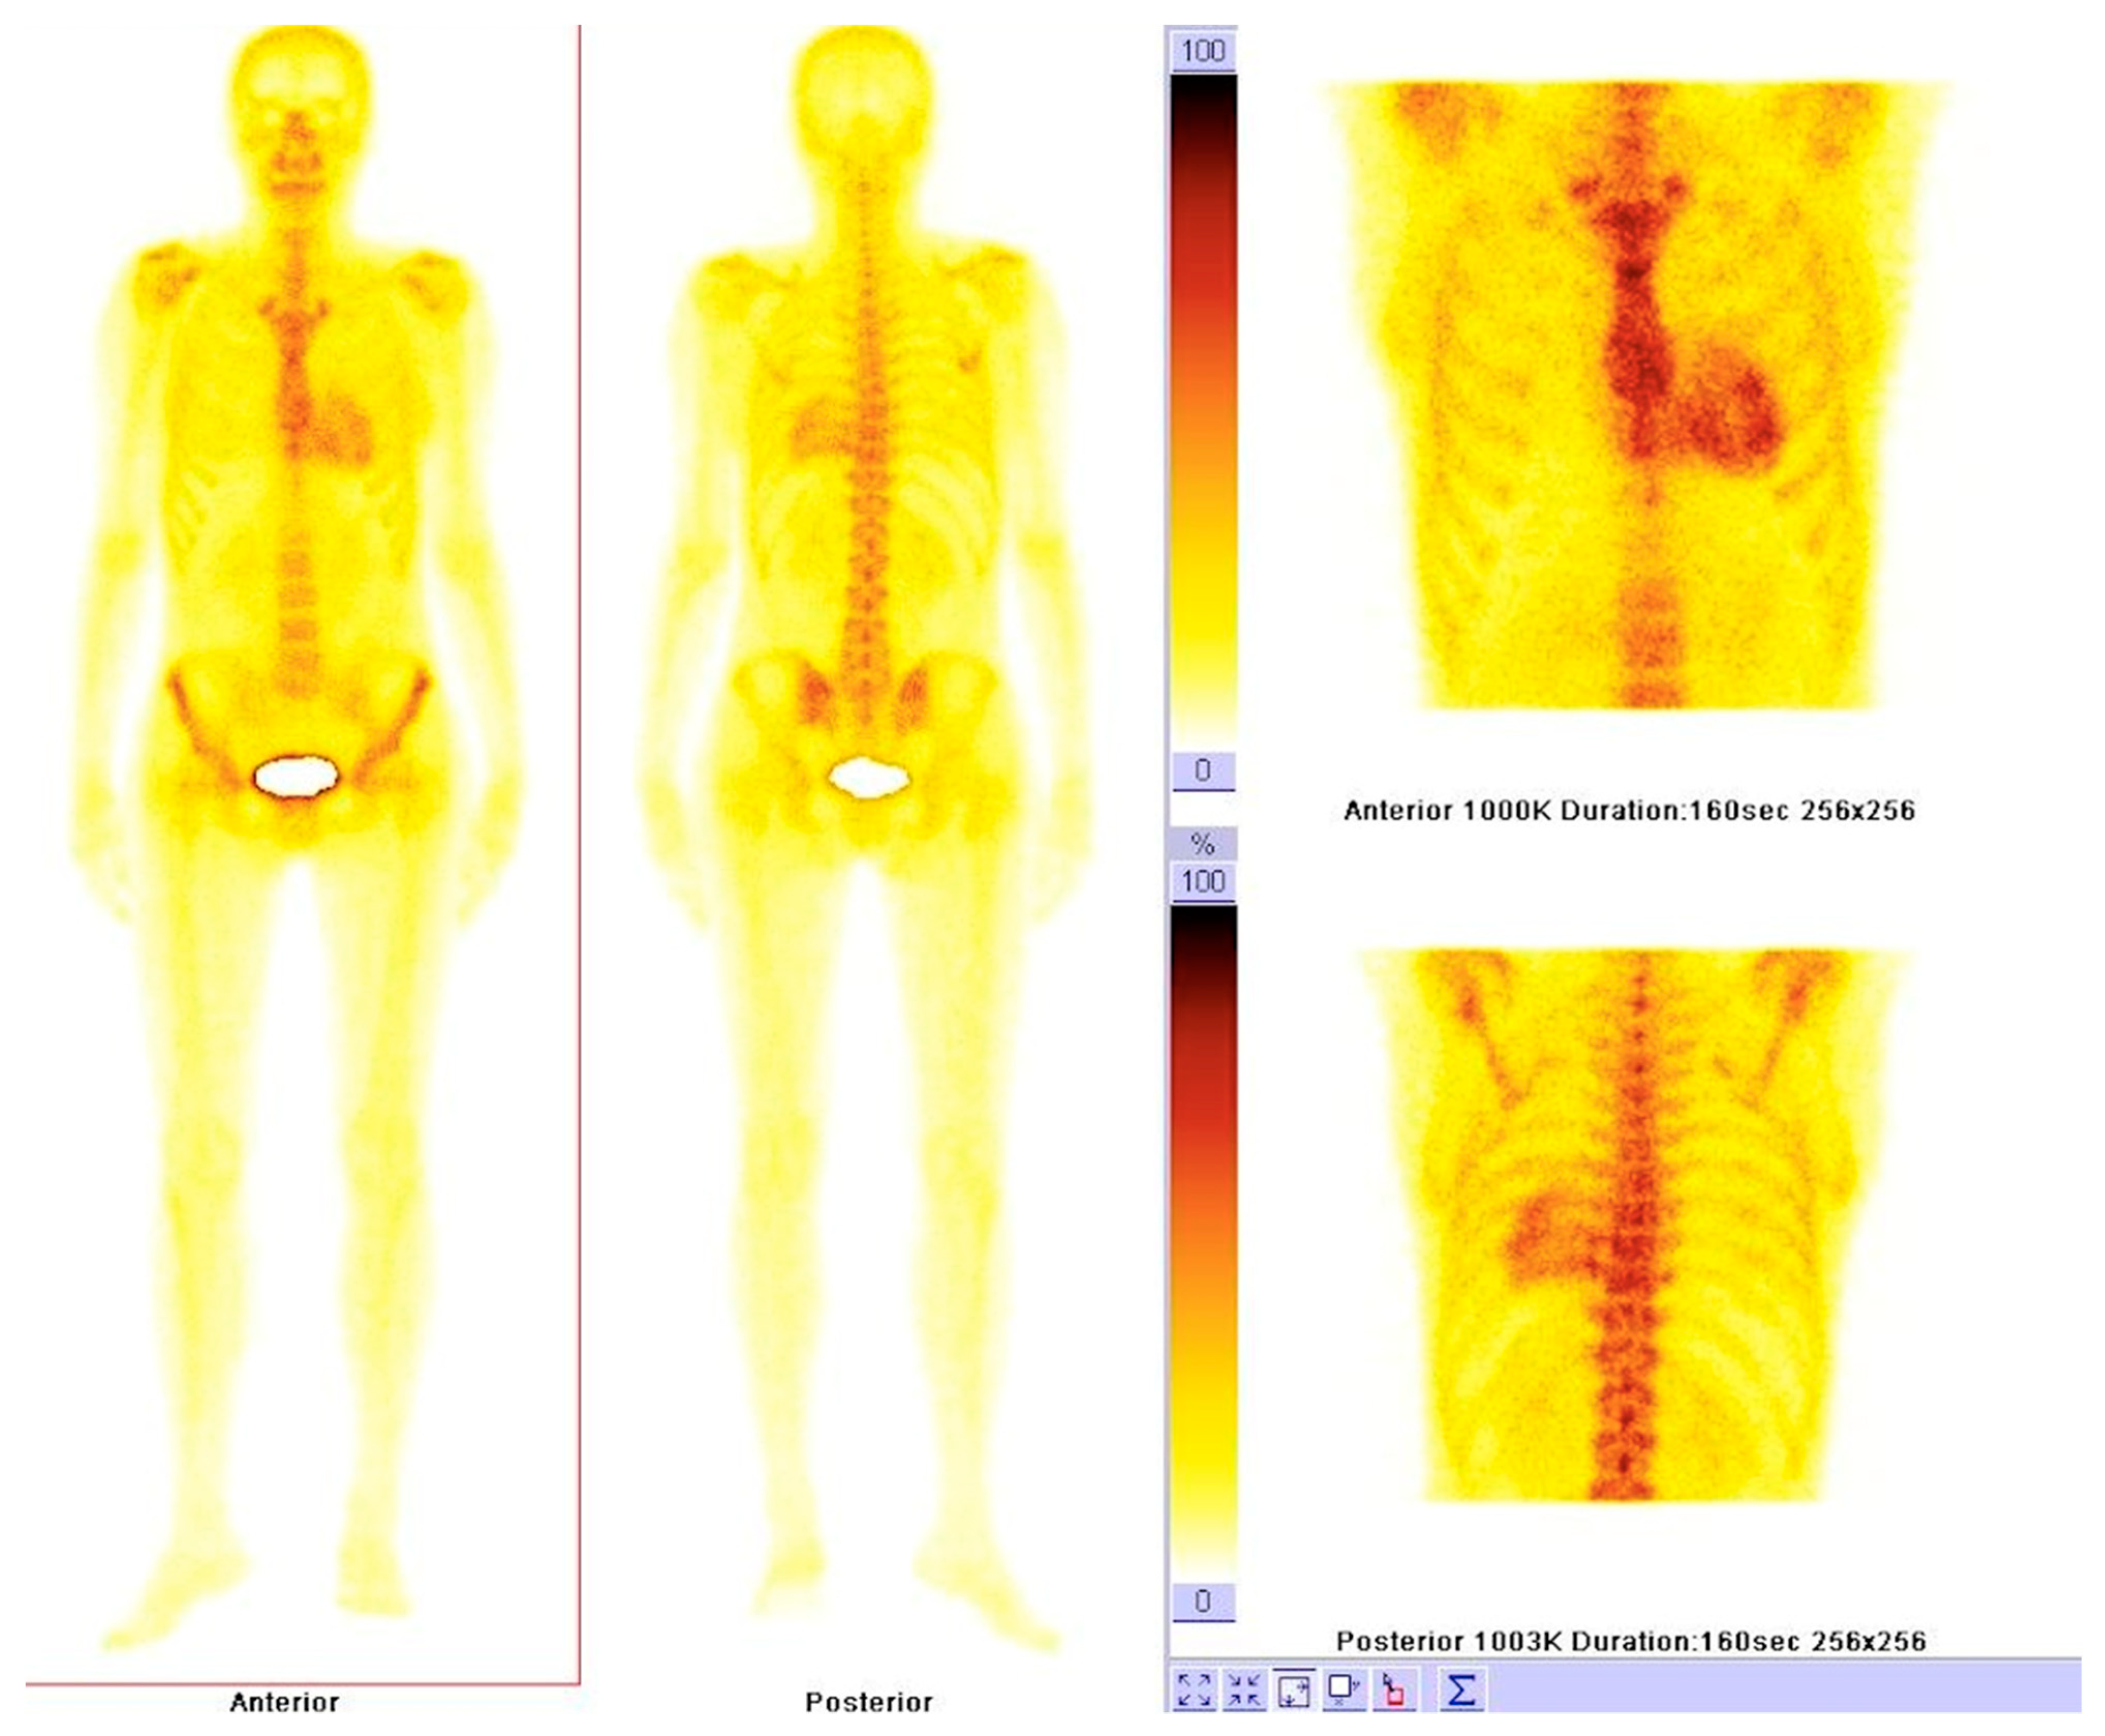

6.1. Nuclear Imaging in Amyloidosis

6.2. Nuclear Imaging in Sarcoidosis